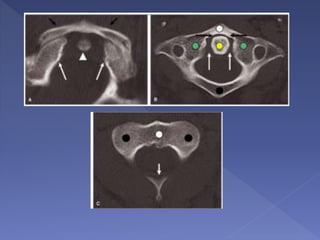

 The apophyseal joints

are normally angled

approximately 35

degrees caudally

 Normal facet joints are

oriented on axial CT

examination so that they

resemble the sides of a

“hamburger bun”